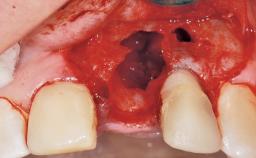

Immediate Flapless Placement of an Implant in a Maxillary Left Central Incisor Site

A 29-year-old female patient presented for treatment to replace the upper left central incisor tooth with an implant- supported restoration. The tooth had been intermittently symptomatic for the previous 12 months. The tooth had originally suffered trauma about 15 years previously. Several endodontic treatments had been performed, including an apicectomy procedure to retain the tooth. The patient was healthy and a non-smoker. She had reasonable expectations in regard to esthetic outcomes and the risk of marginal tissue recession following treatment. At medium smile, the gingival margins of the upper teeth were visible, with a display of 3 to 4 mm of the gingival margins. Gingival recession of tooth 21 and a discrepancy in the gingival levels between teeth 11 and 21 was observable during normal speech and smile.

Placement Protocol Immediate implant placement

Socket Integrity Damage to one or more bone walls

Bone Volume Damage to one or more socket walls